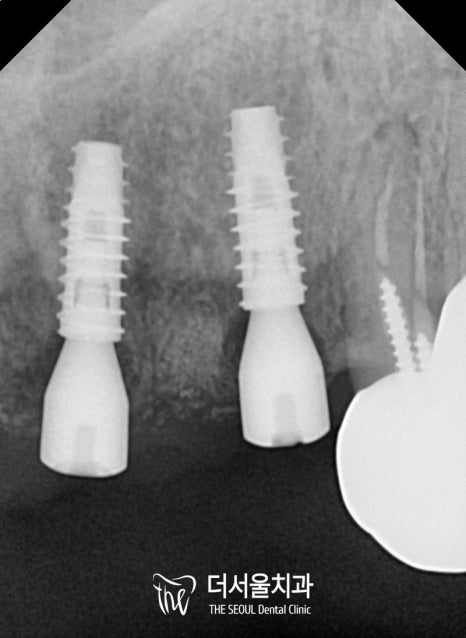

그 후, 컴퓨터 분석을 통하여

어떤 식으로 어떻게 심어줄지

꼼꼼히 살펴보았는데요.

폭이나 두께, 비구개신경을

체크하여 픽스처를 심을 때,

위치 선정을 잘 해드려야 되었습니다.

성남 가천대역치과 에서

컴퓨터 분석 진단 결과에 따라

최적의 위치에 잘 맞춰 심었으며,

남은 것은 뼈와 골결합이

잘 이뤄지길 기다리는 것과

크라운 제작 및 환자의 협조도라 말씀드릴 수 있겠네요.